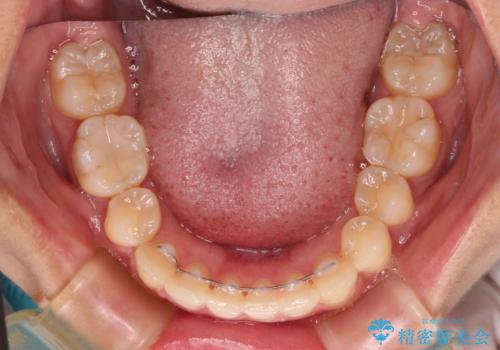

八重歯の抜歯矯正 補助装置とワイヤーを併用したインビザライン矯正治療

- インビザライン・審美装置

インビザラインによる矯正治療を希望されたため、八重歯改善のための抜歯矯正部分や上顎正中の大幅に位置移動は、補助装置やワイヤー矯正を併用し、その後はインビザラインにて行うこととしました。

骨格的に下顎が左側に変位していたため、上下正中を合わせることは困難であることは分かっていましたが、可能な限り合わせることができました。

骨格的なズレがあると仕上げの段階で奥歯の咬み合わせが不安定となるため、予定よりやや長期間となりました。